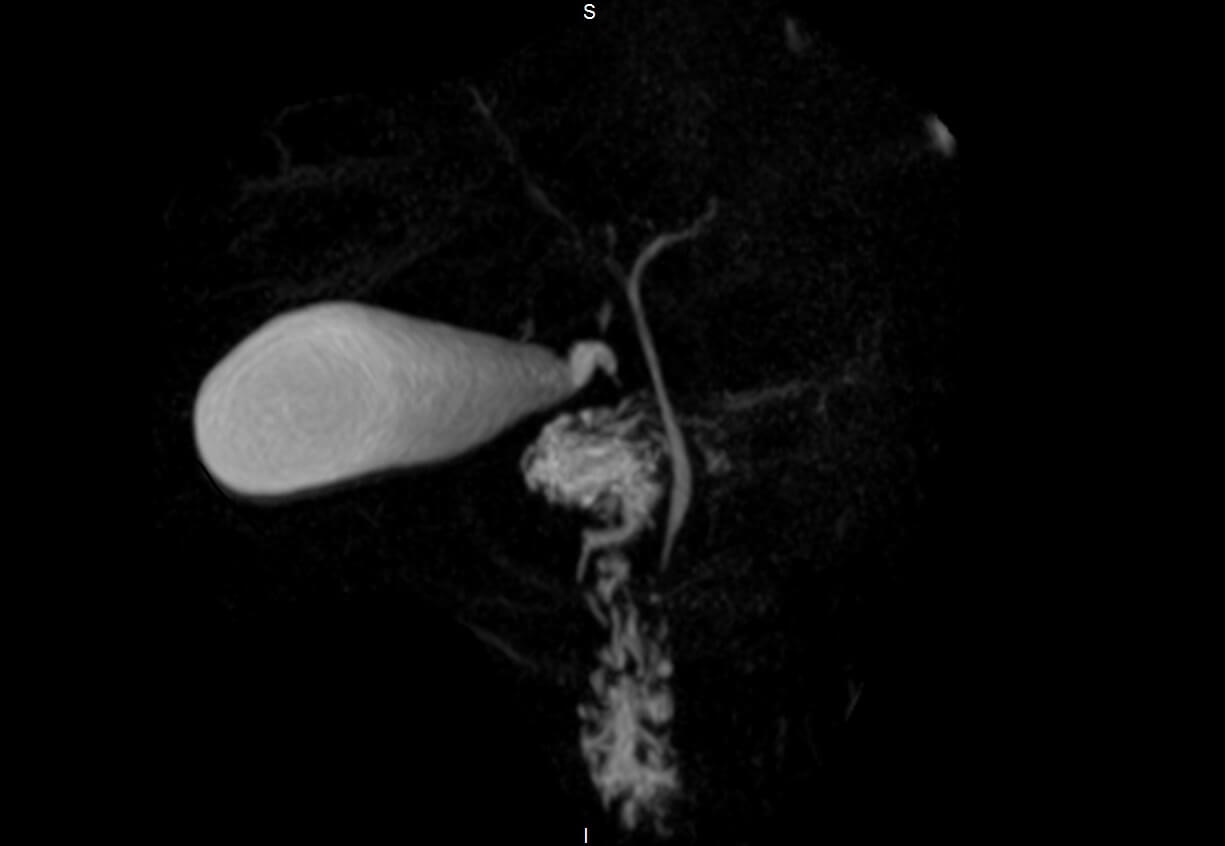

from radiopaedia.org

Choledocholithiasis Radiology Reference Article